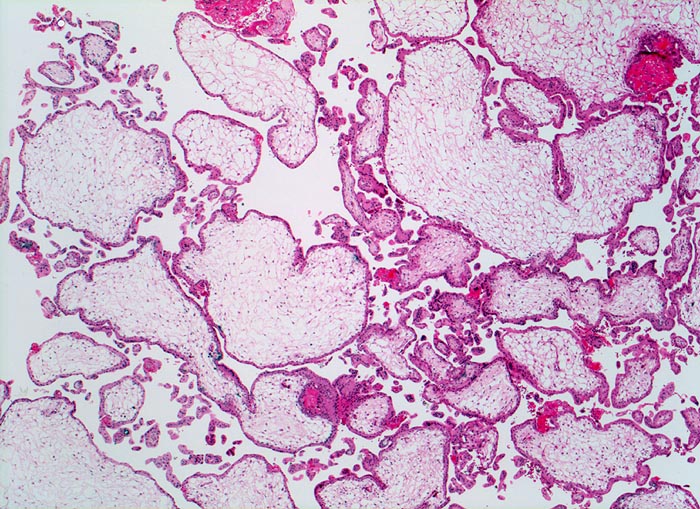

Partialmole bei Triploidie

Grosse plumpe mangelhaft verzweigte Zotten. Mangelhafte Vaskularisation und hydropische Umwandlung des Stromas der Plazentarzotten.

Karyotyp 69, XXX

Im Gegensatz zur Mole nur geringe Trophoblastproliferation. Bei Partialmolen liegt ein diploider Chromosomensatz des Vaters und ein haploider der Mutter vor. Triploidien lassen sich bei etwa 15% chromosomal bedingter Aborte nachweisen. Triploide Früchte erreichen nur extrem selten Geburtsreife.